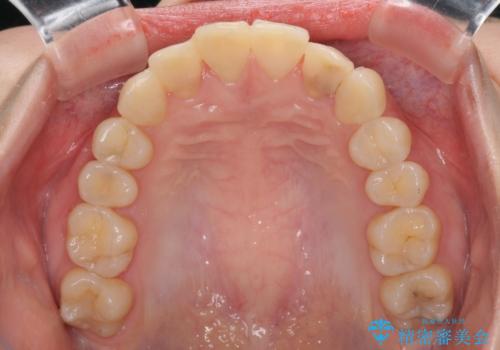

- コンポジットレジンによる治療で継ぎ接ぎだらけになってしまった前歯を綺麗にしたいとのことで来院された患者様です。

必要に応じて根管治療を行い、前歯6歯をオールセラミッククラウンで補綴することとしました。

治療途中に出産を迎えるため、下顎前歯のデコボコを部分矯正で改善し、上下前歯を綺麗に仕上げることとしました。